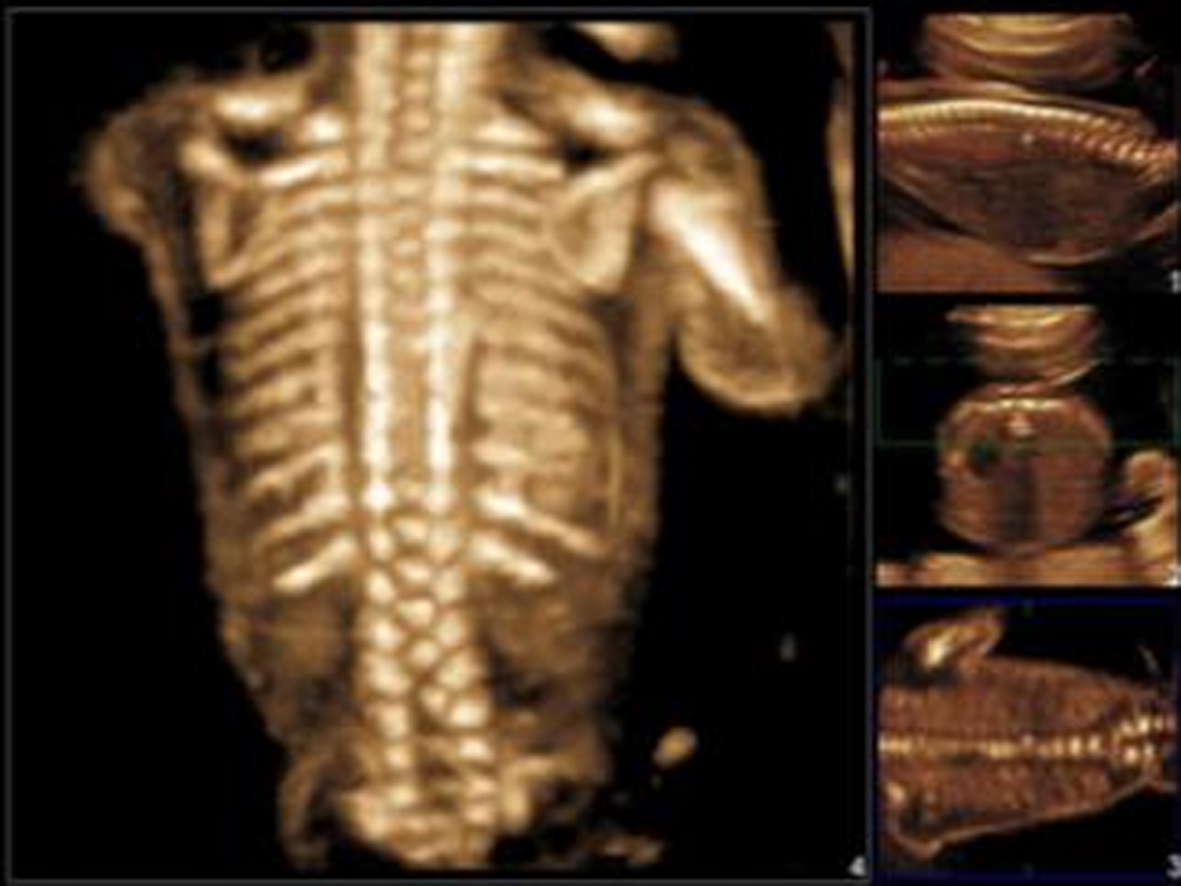

超声显像检查时需要观察矢状切面、横切面和冠状切面(图3,4)。矢状切面显示椎体及一侧椎弓的骨化中心呈现两条串珠状的平行线,在骶尾部收拢合并,因为一个切面只能显示一侧的椎弓,需动态扫描使两侧椎弓都能显示;[f2] 横切面的扫查需要耐心仔细从颈椎到骶尾部依次进行,不同的椎体超声表现不同,第一颈椎呈四边形或圆钝的三角形(图3A),其他呈现等腰三角形,尖端为椎体,指向胎儿腹侧(图3B,图4C、D)。冠状切面,声束靠近皮肤显示两排平行的骨化中心,是双侧椎弓,声束再向胎儿腹侧扫查,可显示一排椎体(图5),透明三维显示可以直观地显示胎儿脊柱的空间结构和形态(图6)。扫查时要注意覆盖在脊柱上的皮肤的完整性,以免遗漏微小的脊柱裂或者隐形脊柱裂,隐形脊柱裂有时仅表现为皮肤鼓起的小泡状无回声。

图6 脊柱三维显示